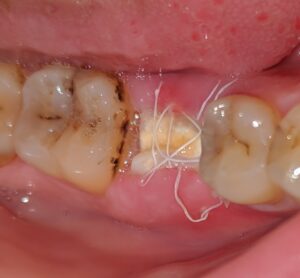

إزالة العظم الزائد

إذا كان هناك نمو زائد، يتم إزالة العظم تحت التخدير الموضعي. ستستغرق فترة النقاهة من 7 إلى 14 يومًا أو أسبوعين، وتوقع بعض الألم.

الوقاية والرعاية بعد العلاج

للوقاية، حافظ على نظافة اللثة بعد خلع السن وتجنب التدخين. استخدام واقي ليلي لصرير الأسنان يساعد. الزيارات المنتظمة لطبيب الأسنان هي الجزء الأهم. نظافة الفم، التي تعتبر أسهل شيء، لها أكبر تأثير في منع هذه الحالة.